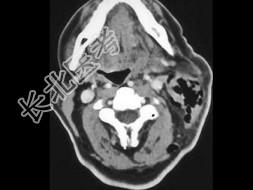

- 单项选择题患者食道部分切除术后,影像检查如图, 最可能的诊断是 ( )

A、脓肿

B、正常术后改变

C、肌肉坏死

D、纤维神经瘤

E、淋巴瘤